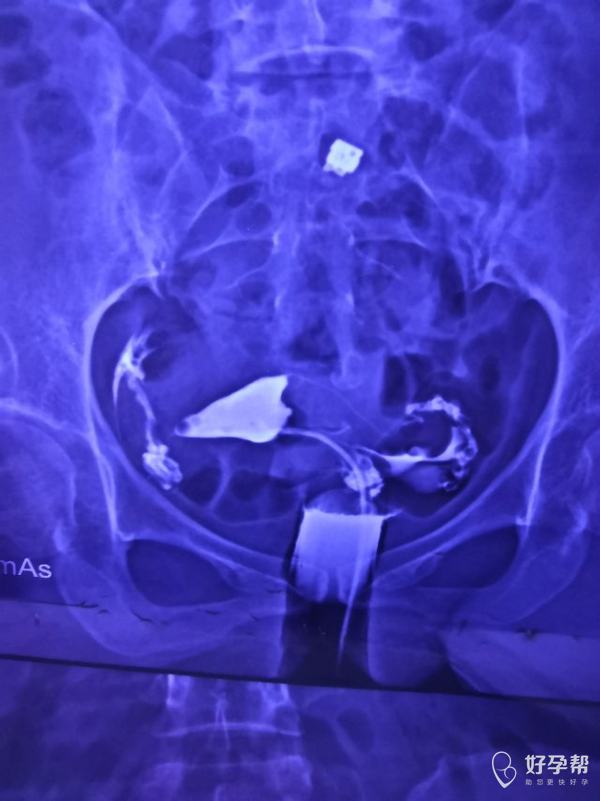

输卵管造影两年前的需要手术吗